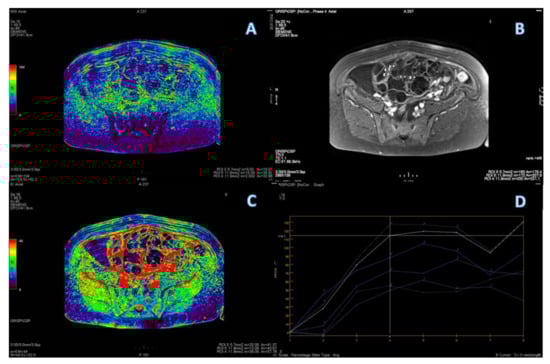

3.1. Primary Tumor DWI

3.3. Primary Tumor DCE

3.4. ROC Curve for LGSC vs. MOC

3.5. ROC Curve for HGSC vs. MOC